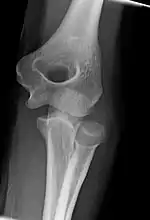

Development

The elbow undergoes dynamic development of ossification centers through infancy and adolescence, with the order of both the appearance and fusion of the apophyseal growth centers being crucial in assessment of the pediatric elbow on radiograph, in order to distinguish a traumatic fracture or apophyseal separation from normal development. The order of appearance can be understood by the mnemonic CRITOE, referring to the capitellum, radial head, internal epicondyle, trochlea, olecranon, and external epicondyle at ages 1, 3, 5, 7, 9 and 11 years. These apophyseal centers then fuse during adolescence, with the internal epicondyle and olecranon fusing last. The ages of fusion are more variable than ossification, but normally occur at 13, 15, 17, 13, 16 and 13 years, respectively.[16] In addition, the presence of a joint effusion can be inferenced by the presence of the fat pad sign, a structure that is normally physiologically present, but pathologic when elevated by fluid, and always pathologic when posterior.[17]

Fractures

There are three bones at the elbow joint, and any combination of these bones may be involved in a fracture of the elbow. Patients who are able to fully extend their arm at the elbow are unlikely to have a fracture (98% certainty) and an X-ray is not required as long as an olecranon fracture is ruled out.[27] Acute fractures may not be easily visible on X-ray.[28]

Arthritis

Elbow arthritis is usually seen in individuals with rheumatoid arthritis or after fractures that involve the joint itself. When the damage to the joint is severe, fascial arthroplasty or elbow joint replacement may be considered.[32]